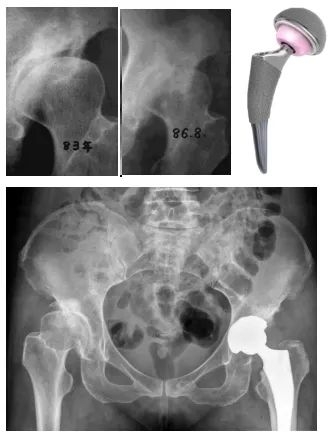

(正常髋关节X线(左图)显示髋臼对股骨头的包容良好;发育不良髋关节X线(右图)显示髋臼对股骨头的包容不足。)我国人口众多,普查筛查水平相对不足,导致患者数量巨大,而疾病发现晚和处理晚。通常青少年或成人的DDH初期无明显临床症状,但随着病情进展,患者会出现髋关节周围疼痛。

(35岁患者诊断DDH后未及时矫正,3年发展为髋骨关节炎行全髋关节置换术)虽然目前的人工全髋关节置换手术已经非常成熟,效果满意,但是仍然存在人工关节假体使用寿命年限的问题,而且也存在感染和脱位等并发症。尤其是年轻人,还不得不面对人工关节使用年限到了之后再次翻修的问题。因此如何避免早期DDH患者发展为髋骨关节炎,成为了关节外科医生不得不面对的事情。